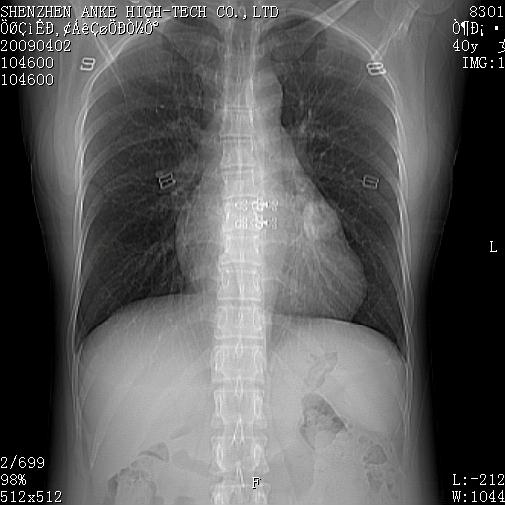

以下是引用随光逐影在2009-4-2 12:16:00的发言:[br]考虑左肺下叶背段继发性肺结核,结核球形成;建议追踪复查。

以下是引用gudu医生在2009-4-2 11:27:00的发言:[br]周围型肺癌

以下是引用卜一在2009-4-2 13:31:00的发言:[br][br] [br] 空洞壁厚不均 胸膜凹陷征。周围型肺癌可能 不排除干酪坏死型肺结核及坏死性肉芽肿。 [br] [br]支持!

以下是引用ct诊断高手在2009-4-2 13:04:00的发言:[br]空洞壁厚不均 胸膜凹陷征。周围型肺癌可能 不排除干酪坏死型肺结核及坏死性肉芽肿。